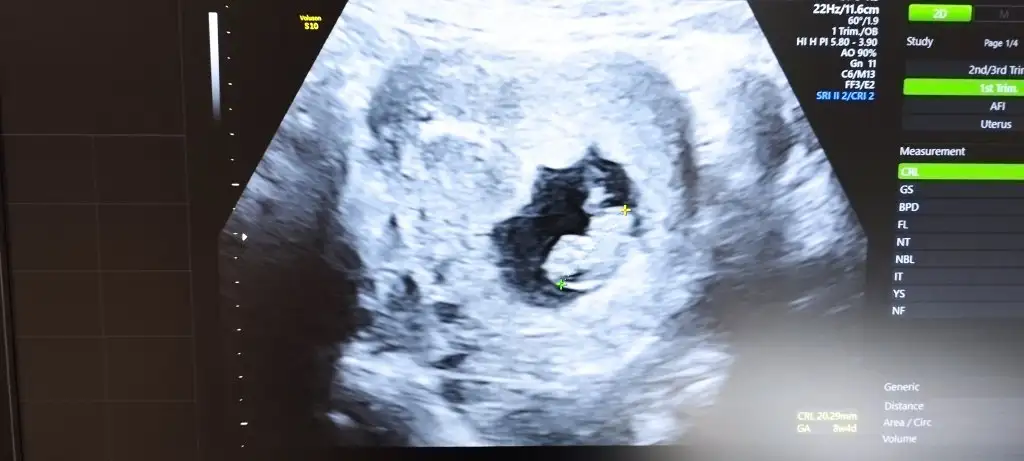

Merhaba bebeğim 10 haftalık. Benim içinde yorum yapar mısınız. teşekkürler <3Selam Kızlarbir çok kişi gruplardan beni bilir. Yine yetiştim imdatlara

5 ve 14. haftaya kadar olan ultrason fotolarınızı paylaşın. Vajinadan mı yoksa karından mı çekildiğini ve kaç haftalık olduğunu da mutlaka belirtin.